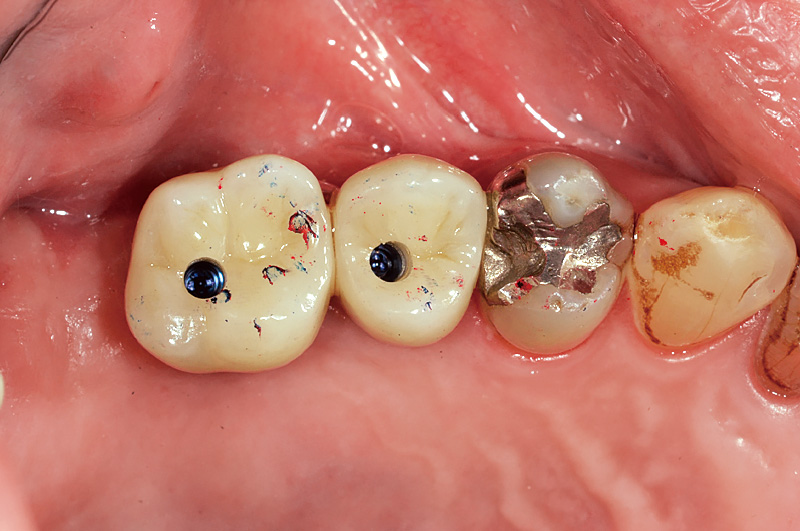

![[写真] 装着](/academic/dentalmagazine/wp-content/uploads/sites/2/2025/11/195-10_photo13.jpg)

図13 装着

今回二ケイ酸リチウムを使用し上部構造を作製することで、前方歯とも色調的に調和のとれた口腔内を再現可能としている。CERECをはじめとしたデジタル機器との相性の良さは、二ケイ酸リチウムやジルコニアなど高品位なマシナブルセラミック材料との相性の良さを示している。 -